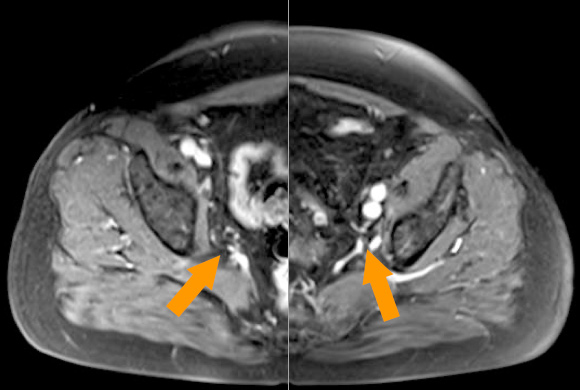

Die Abbildungen zeigten CT und MRT-Scans eines Patienten mit Lymphknotenmetastasen bei einem Prostatakarzinom. Der Patient hatte sich einer Hormonentzugstherapie (ADT Androgen-Deprivations-Therapie) unterzogen, die nicht mehr wirkte. Der PSA-Spiegel war auf 8,65 ng/ml angestiegen. Die Lmyphknotenmetastasen (MRT-Bild rechts oben, Pfeile) sind tief im Becken im Bereich der großen Beckengefäße (Iliakalgefäße) und direkt neben den Ischiasnerven (Nervi ischiadici) lokalisiert. Das Bild rechts oben zeigt die Einbringung der Elektroden in die Lymphknoten im Computertomographen mit Hilfe des infrarotgesteuerten virtual Reality Systems Cascination. Das CT-Bild links unten zeigt die Elektroden in ihrem Verlauf von der Bauchwand bis in die metastasenbefallenen Lymphknoten. Das MRT-Bild rechts unter zeigt das Ergebnis fünf Monate später: Die Lymphknotenmetastasen sind vollständig verschwunden, der PSA-Spiegel sank auf 0,06 ng/ml ab.